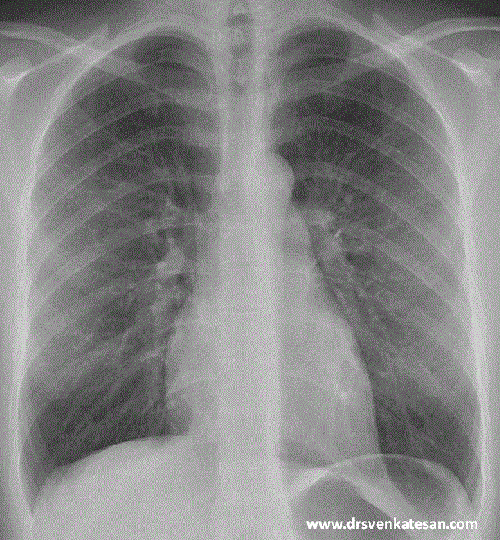

Since I have struggled with X ray orientation of heart chambers in my early days (Still i do sometimes!) Just thought , why we are not fusing a X-ray with a given patients echocardiogram that will help understand the chamber anatomy .

Fusion Image of X ray chest PA view with apical 4 chamber in ECHO. (Rotated to specified angle to match heart border)